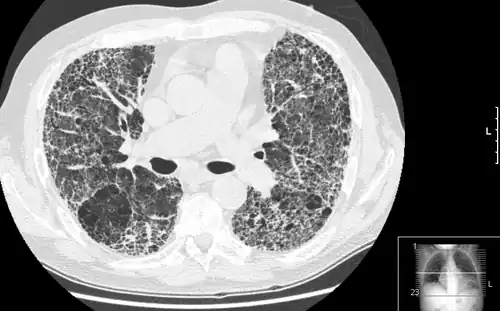

HRCT of lung showing extensive fibrosis possibly from usual interstitial pneumonitis. There is also a large bulla.

The diagnosis can be confirmed by lung biopsy.[3] A video-assisted thoracoscopic surgery (VATS) under general anesthesia may be needed to obtain enough tissue to make an accurate diagnosis. This kind of biopsy involves placement of several tubes through the chest wall, one of which is used to cut off a piece of lung for evaluation. The removed tissue is examined histopathologically by microscopy to confirm the presence and pattern of fibrosis as well as other features that may indicate a specific cause, such as specific types of mineral dust or possible response to therapy, e.g. a pattern of so-called non-specific interstitial fibrosis.